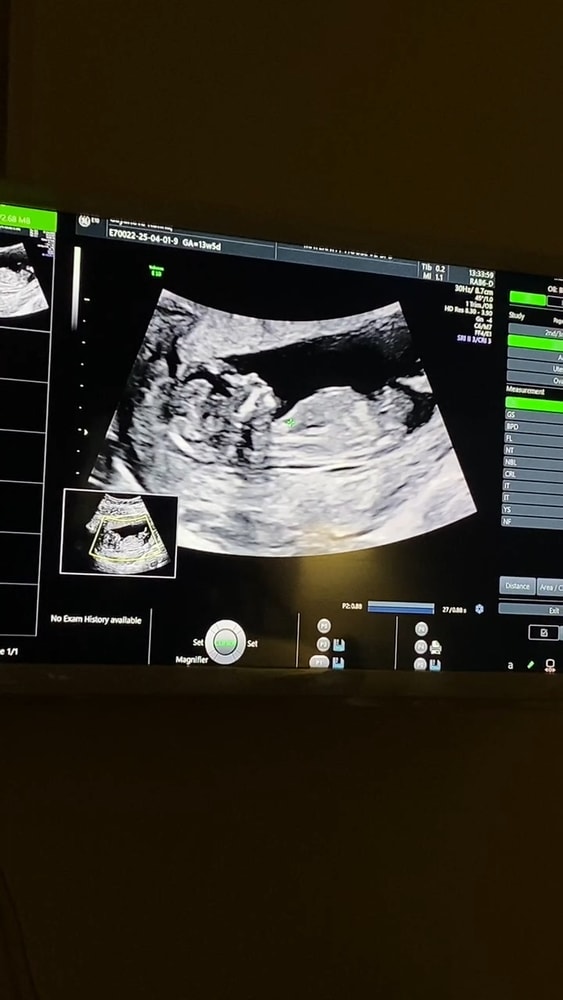

Первый скрининг ✅️

Поздравляю! Я вижу девочку!

Малышок прелестный! Носик пуговка, губки бантиком. Растите большими!

Пол не сказали? Картинка хорошая, мальчик, возможно)

За восходом, сказали,что рано еще) а как вы это видите?)

Руфина, я плохо вижу по узи, но чувствую, что будет мальчик)

Nya, девочка:-)